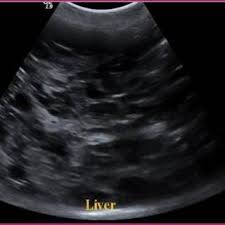

Dogs often exhibit typical symptoms of liver disease, but some tumors may be asymptomatic for some time. It is therefore difficult to diagnose. Changes in your dog's bathroom behavior could potentially indicate cancer in the bladder or kidneys. Symptoms of canine liver cancer include: The most common tumors derived from the liver are.

Liver Cancer And Tumors In Dogs Free Brochure On Treatment Options from www.dog-health-guide.org While symptoms may vary, and some dogs are asymptomatic (meaning they show no symptoms), there are some signs of liver cancer in. After doing some research on dog cancer symptoms, christina took her pup to the vet, who confirmed that pickles's weight loss and lethargy were indeed signs of a tumor. The liver can regrow itself, so dogs can recover even if a large amount of the liver has to be removed, but the veterinarian will need to ensure the liver is functioning. If your dog has symptoms of liver dysfunction, cancer may be suspected as the cause, based on age and the elimination of other factors. Symptoms of canine liver cancer include: Primary liver cancer occurs more frequently in older dogs (10 years of age or older). What are some of the symptoms of cancer in dogs? Loss of appetite that can lead to weight loss.

The manifested cancer symptoms in dogs vary according to the affected portion. Canine liver cancer can be primary (originated in the liver) or metastatic (originated somewhere else and spread to the liver). However, as the disease becomes worst it. If your dog has liver cancer, chemotherapy or radiation could. Discomfort in the upper abdomen on the right side. Malignant liver tumors have been reported to metastasize to other organs such as regional lymph nodes, lungs. Liver cancer in dogs is one of the most complex canine cancers. Get vaccinated against hepatitis b. Our channel would be showing cancer symptoms, signs of breast cancer, horoscopo de hoy cancer, home remedy for cancer, natural remedies for cancer, foods for liver cancer, foods for skin cancer, foods for stomach cancer, foods liver disease problems in dogs treatment & homemade recipe. What are some of the symptoms of cancer in dogs? However, having said this it is more common for the signs and symptoms of the disease are quite difficult to detect mainly because they are fairly indistinct. According to bark.com, 1 in 4 dogs will develop a cancerous tumor. Symptoms of liver cancer in dogs can be vague and indistinct, such as appetite loss, lethargy, and vomiting.